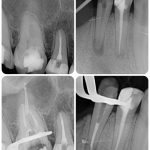

To szybkie, bezpieczne i bardzo precyzyjne badanie radiologiczne, które pozwala nam dokładnie ocenić stan jednego zęba lub niewielkiego obszaru jamy ustnej. Dzięki temu możemy wykryć wszelkie zmiany patologiczne, takie jak próchnica, zakażenia czy urazy.

🔍 Szybka diagnoza – wyniki w kilka minut!

🔍 Minimalna dawka promieniowania – bezpieczna dla zdrowia.

🔍 Dokładność – idealne do oceny pojedynczych zębów.